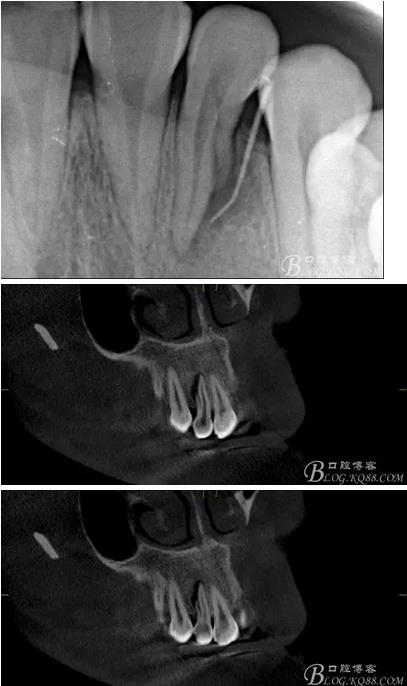

(1) 檢查:12唇側(cè)牙齦可見竇道,牙體顏色較鄰牙暗,無光澤,形態(tài)完整無缺損,唇側(cè)及近遠中向未提及牙周袋。腭側(cè)齦緣輕度紅腫,舌側(cè)窩可探及裂溝,可見浸墨狀痕跡,沿裂溝舌側(cè)探診牙周袋深大于11mm,除患牙外全口牙周狀況良好,為探及牙周袋,牙齦色粉紅。邊緣菲薄,質(zhì)地堅韌。12冷熱診無反應(yīng),叩診(+-),無明顯松動,無咬合創(chuàng)傷。12根尖x線片示,根管中三分之一中可見一斜向線樣透射影像根尖區(qū)及遠中根三分之一可見低密度透射暗影,錐形束CT示12根尖區(qū)唇腭向骨吸收已穿通,根面溝達根中三分之一卷曲分出另一牙根,再未見其他明顯的根管系統(tǒng)。